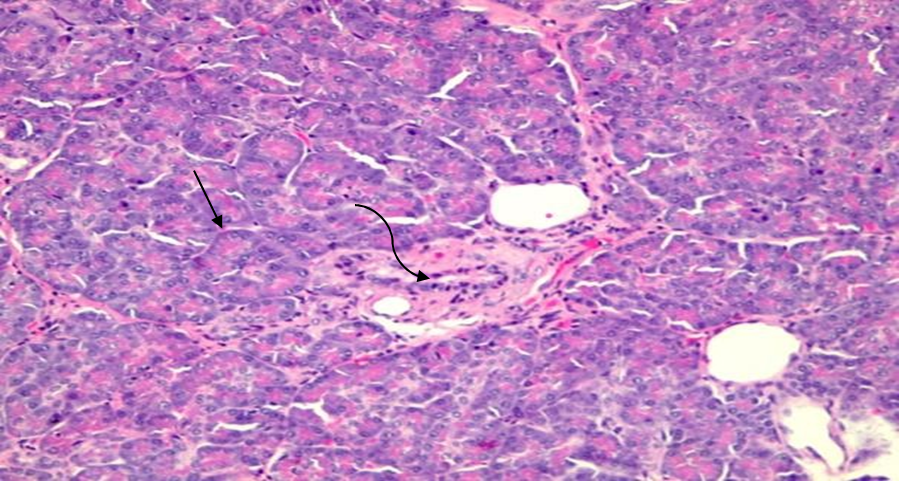

Figure 4 Histopathology of pancreatic heterotopia in the gallbladder of a 51-year-old woman using a hematoxylin and eosin stain demonstrates benign pancreatic tissue with acini (straight arrow) and ducts (curved arrow). No Langerhans islets are identified. [400x view]